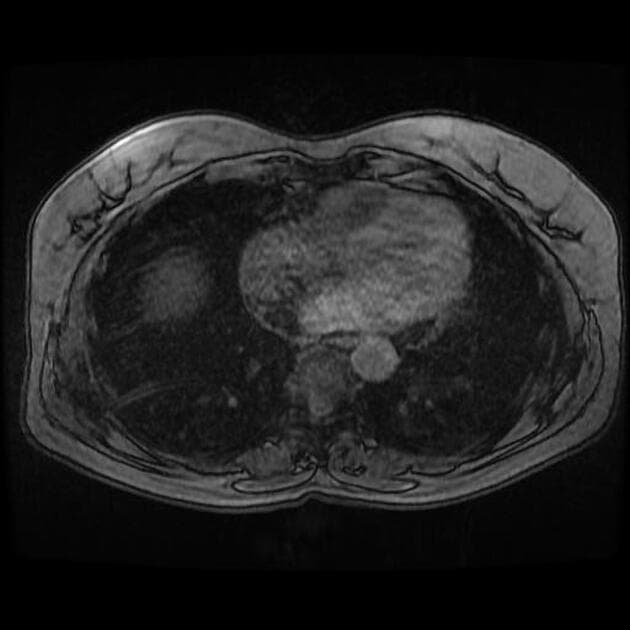

Chụp cộng hưởng từ theo dõi

Hai tổn thương khu trú ở gan được xác định:

Kết luận: Hai tổn thương khu trú ở gan, hình ảnh cộng hưởng từ phù hợp với tăng sản khu trú dạng nốt (focal nodular hyperplasia).

Hai tổn thương bắt thuốc ở phân đoạn 6 và 3, vùng trung tâm giảm tỷ trọng (không bắt thuốc) và không có hiện tượng thải thuốc (washout).

Hình ảnh điển hình của tăng sản khu trú dạng nốt (focal nodular hyperplasia), là một trong số ít các tổn thương có khả năng tích tụ mạnh thuốc cản quang đặc hiệu tế bào gan.